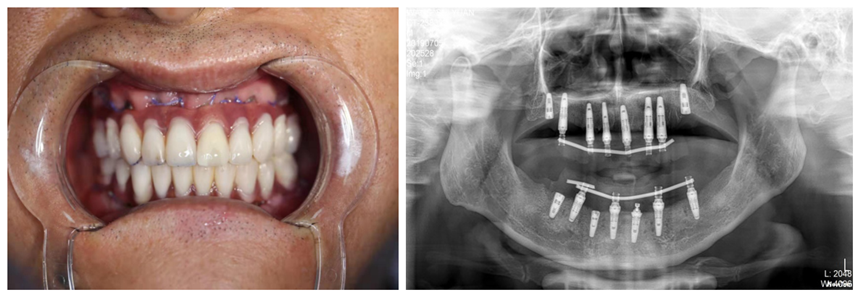

錢主任給予王先生口腔檢查,發(fā)現(xiàn)他有嚴(yán)重的牙周病,下頜牙基本全部脫落,上頜后牙也全部脫落只剩下幾顆松動(dòng)的前牙,根本無法咀嚼食物。給予口腔CT檢查后,錢主任發(fā)現(xiàn),王先生由于長期缺牙,牙槽骨已經(jīng)嚴(yán)重吸收,骨條件不理想,但鑒于王先生迫切的希望能盡快恢復(fù)美觀及咀嚼功能,經(jīng)過充分溝通及反復(fù)討論與完善調(diào)節(jié)計(jì)劃,終決定給予王先生一次性拔除全部松動(dòng)牙后行全口種植修復(fù)的方法,讓王先生在當(dāng)天種植術(shù)后當(dāng)天就能擁有一口整齊、漂亮的牙齒。

由于全口種植技術(shù)要求較高,患者王先生的骨條件又不理想,醫(yī)生在術(shù)前利用王先生的牙齒模型和CBCT數(shù)據(jù),為其制作了數(shù)字化種植手術(shù)導(dǎo)板,使手術(shù)更微創(chuàng)、更。從開始拔牙、種植到制作臨時(shí)義齒,再到后佩戴調(diào)試完畢,口腔科種植團(tuán)隊(duì)整整用了12小時(shí)。當(dāng)王先生看到自己的一口新牙時(shí),露出了滿意的笑容,開心地說:“一天的辛苦是值得的!謝謝你們,我終于有一口好牙啦!”

術(shù)前片

術(shù)后片